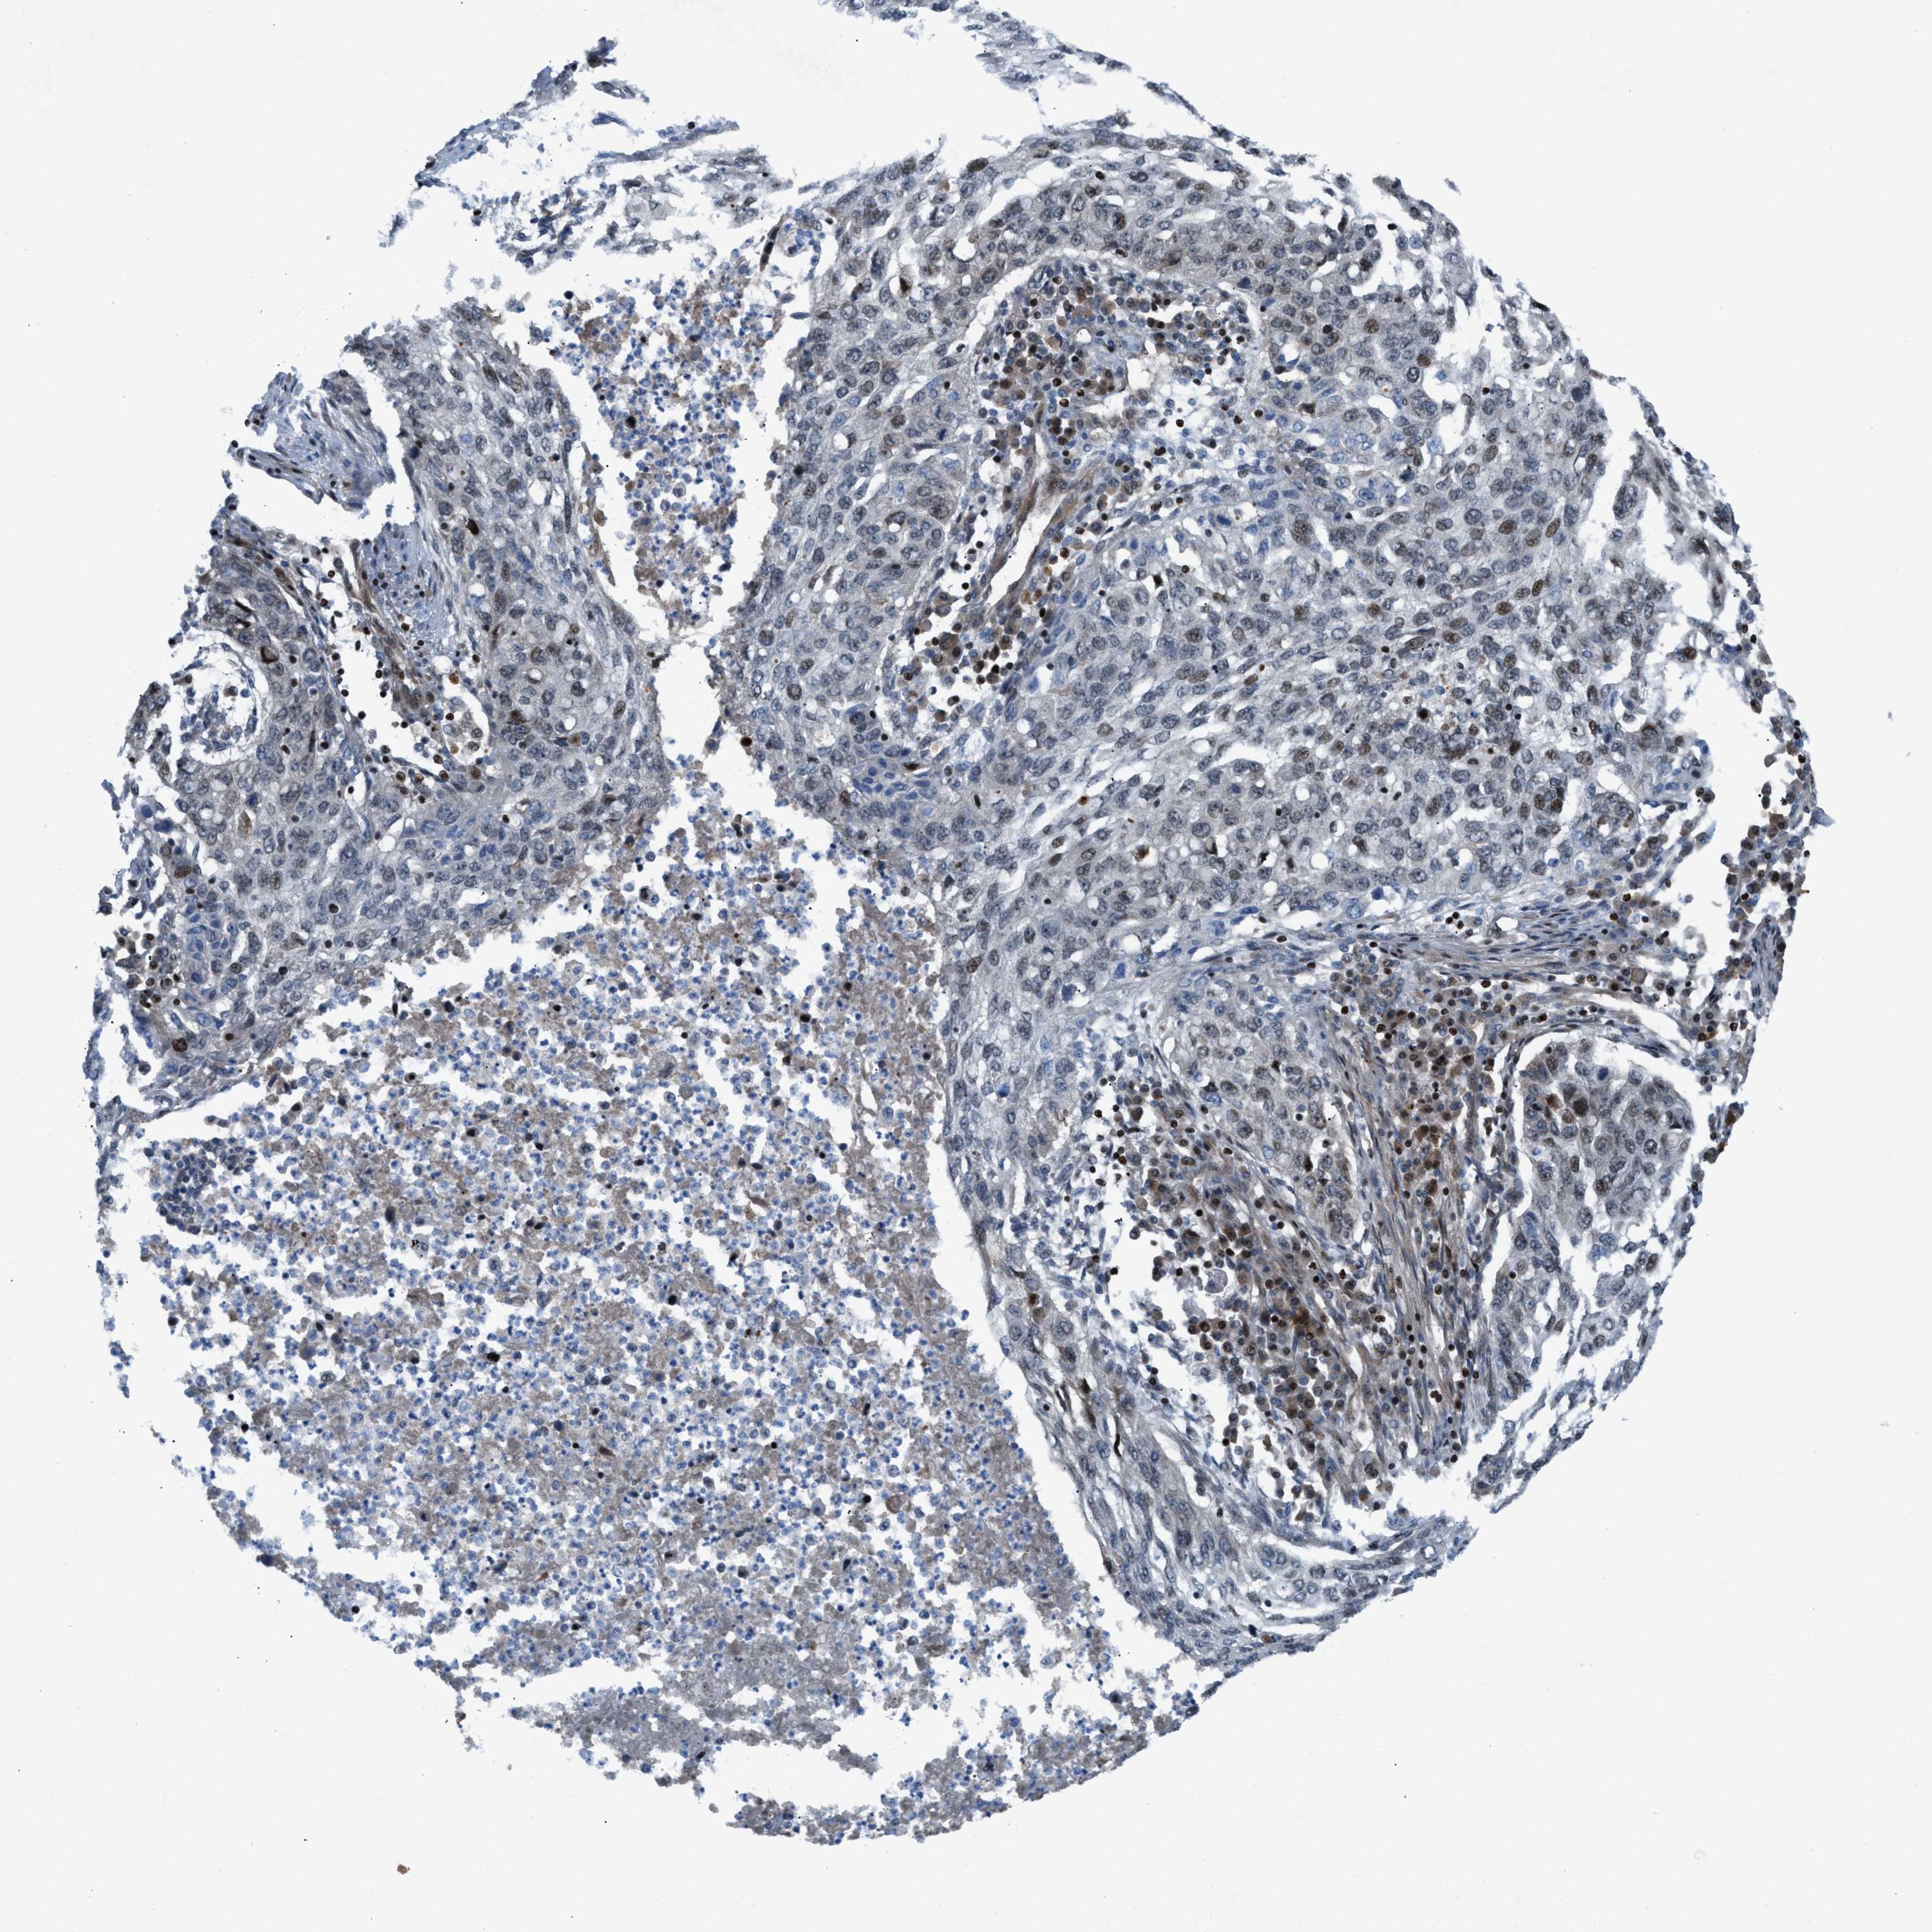

LUNG SQUAMOUS CELL CARCINOMA (TCGA) - Interactive survival scatter ploti

The Survival Scatter plot shows the clinical status (i.e. dead or alive) for all individuals in the patient cohort, based on the same data that underlies the corresponding Kaplan-Meier plots. Patients that are alive at last time for follow-up are shown in blue and patients who have died during the study are shown in red.

The x-axis shows the expression levels (FPKM) of the investigated gene in the tumor tissue at the time of diagnosis. The y-axis shows the follow-up time after diagnosis (years). Both axes are complimented with kernel density curves demonstrating the data density over the axes. The top density plot shows the expression levels (FPKM) distribution among dead (red) and alive patients (blue). The right density plot shows the data density of the survived years of dead patients with high and low expression levels respectively, stratified using the cutoff indicated by the vertical dashed line through the Survival Scatter plot. This cutoff is automatically defined based on the FPKM cutoff that minimizes the p-score. The cutoff can be changed by dragging the vertical line or by entering a cutoff value in the square labeled "Current cut-off".

Under the Survival Scatter plot the p-score landscape (black curve; left axis) is shown together with dead median separation (red curve; right axis). Dead median separation is the difference in median mRNA expression between patients who have died with high and low expression, respectively. It is calculated as follows: median FPKM expression of dead patients with high expression - median FPKM expression of dead patients with low expression. This is intended to aid the user in visually exploring custom cutoffs and the associated p-scores and dead median separation.

Individual patient data is displayed and can be filtered by clicking on one or more of the category buttons on the top of the page. Categories describing expression level and patient information include: high, low, alive, dead, female, male and tumor stages. The scale of the x-axis can be toggled between linear and log-scale by clicking on the "x log" button. Mouse-over function shows TCGA ID, patient information and mRNA expression (FPKM) for each patient.

& Survival analysisi

Kaplan-Meier plots summarize results from analysis of correlation between mRNA expression level and patient survival. Patients were divided based on level of expression into one of the two groups "low" (under cut off) or "high" (over cut off). X-axis shows time for survival (years) and y-axis shows the probability of survival, where 1.0 corresponds to 100 percent.

ZNF276 is not prognostic in Lung Squamous Cell Carcinoma (TCGA)

Best expression cut offi

Based on the FPKM value of each gene, patients were classified into two groups and association between prognosis (survival) and gene expression (FPKM) was examined. The best expression cut-off refers the FPKM value that yields maximal difference with regard to survival between the two groups at the lowest log-rank P-value. Best expression cut-off was selected based on survival analysis .

When clicking on this number, the vertical dashed line indicating cut-off, the interactive survival plot, and the Kaplan-Meier curve will be adjusted to show results based on the best expression cut-off.

: 6.94

Median expressioni

Median expression refers to the median FPKM value calculated based on the gene expression (FPKM) data from all patients in this dataset. When clicking on this number, the vertical dashed line indicating cut-off, the interactive survival plot, and the Kaplan-Meier curve will be adjusted to show results based on the median expression.

: N/A

Median follow up timei

Median follow up time refers to the median time (years) after diagnosis with this type of cancer, based on clinical data from all patients in this dataset.

P scorei

Log-rank P value for Kaplan-Meier plot showing results from analysis of correlation between mRNA expression level and patient survival.

N/A

5-year survival highi

5-year survival for patients with higher expression than the expression cutoff.

For melanoma and glioma, 3-year survival is shown.

5-year survival lowi

5-year survival for patients with lower expression than the expression cutoff.

TCGA RNA samplesi

RNA-seq data is reported as average FPKM (number Fragments Per Kilobase of exon per Million reads), generated by the The Cancer Genome Atlas (TCGA) .

Normal distribution across the dataset is visualized with box plots, shown as median and 25th and 75th percentiles. Points are displayed as outliers if they are above or below 1.5 times the interquartile range. FPKM values of the individual samples are presented next to the box plot.

Average pTPM 5.9

Number of samples 489